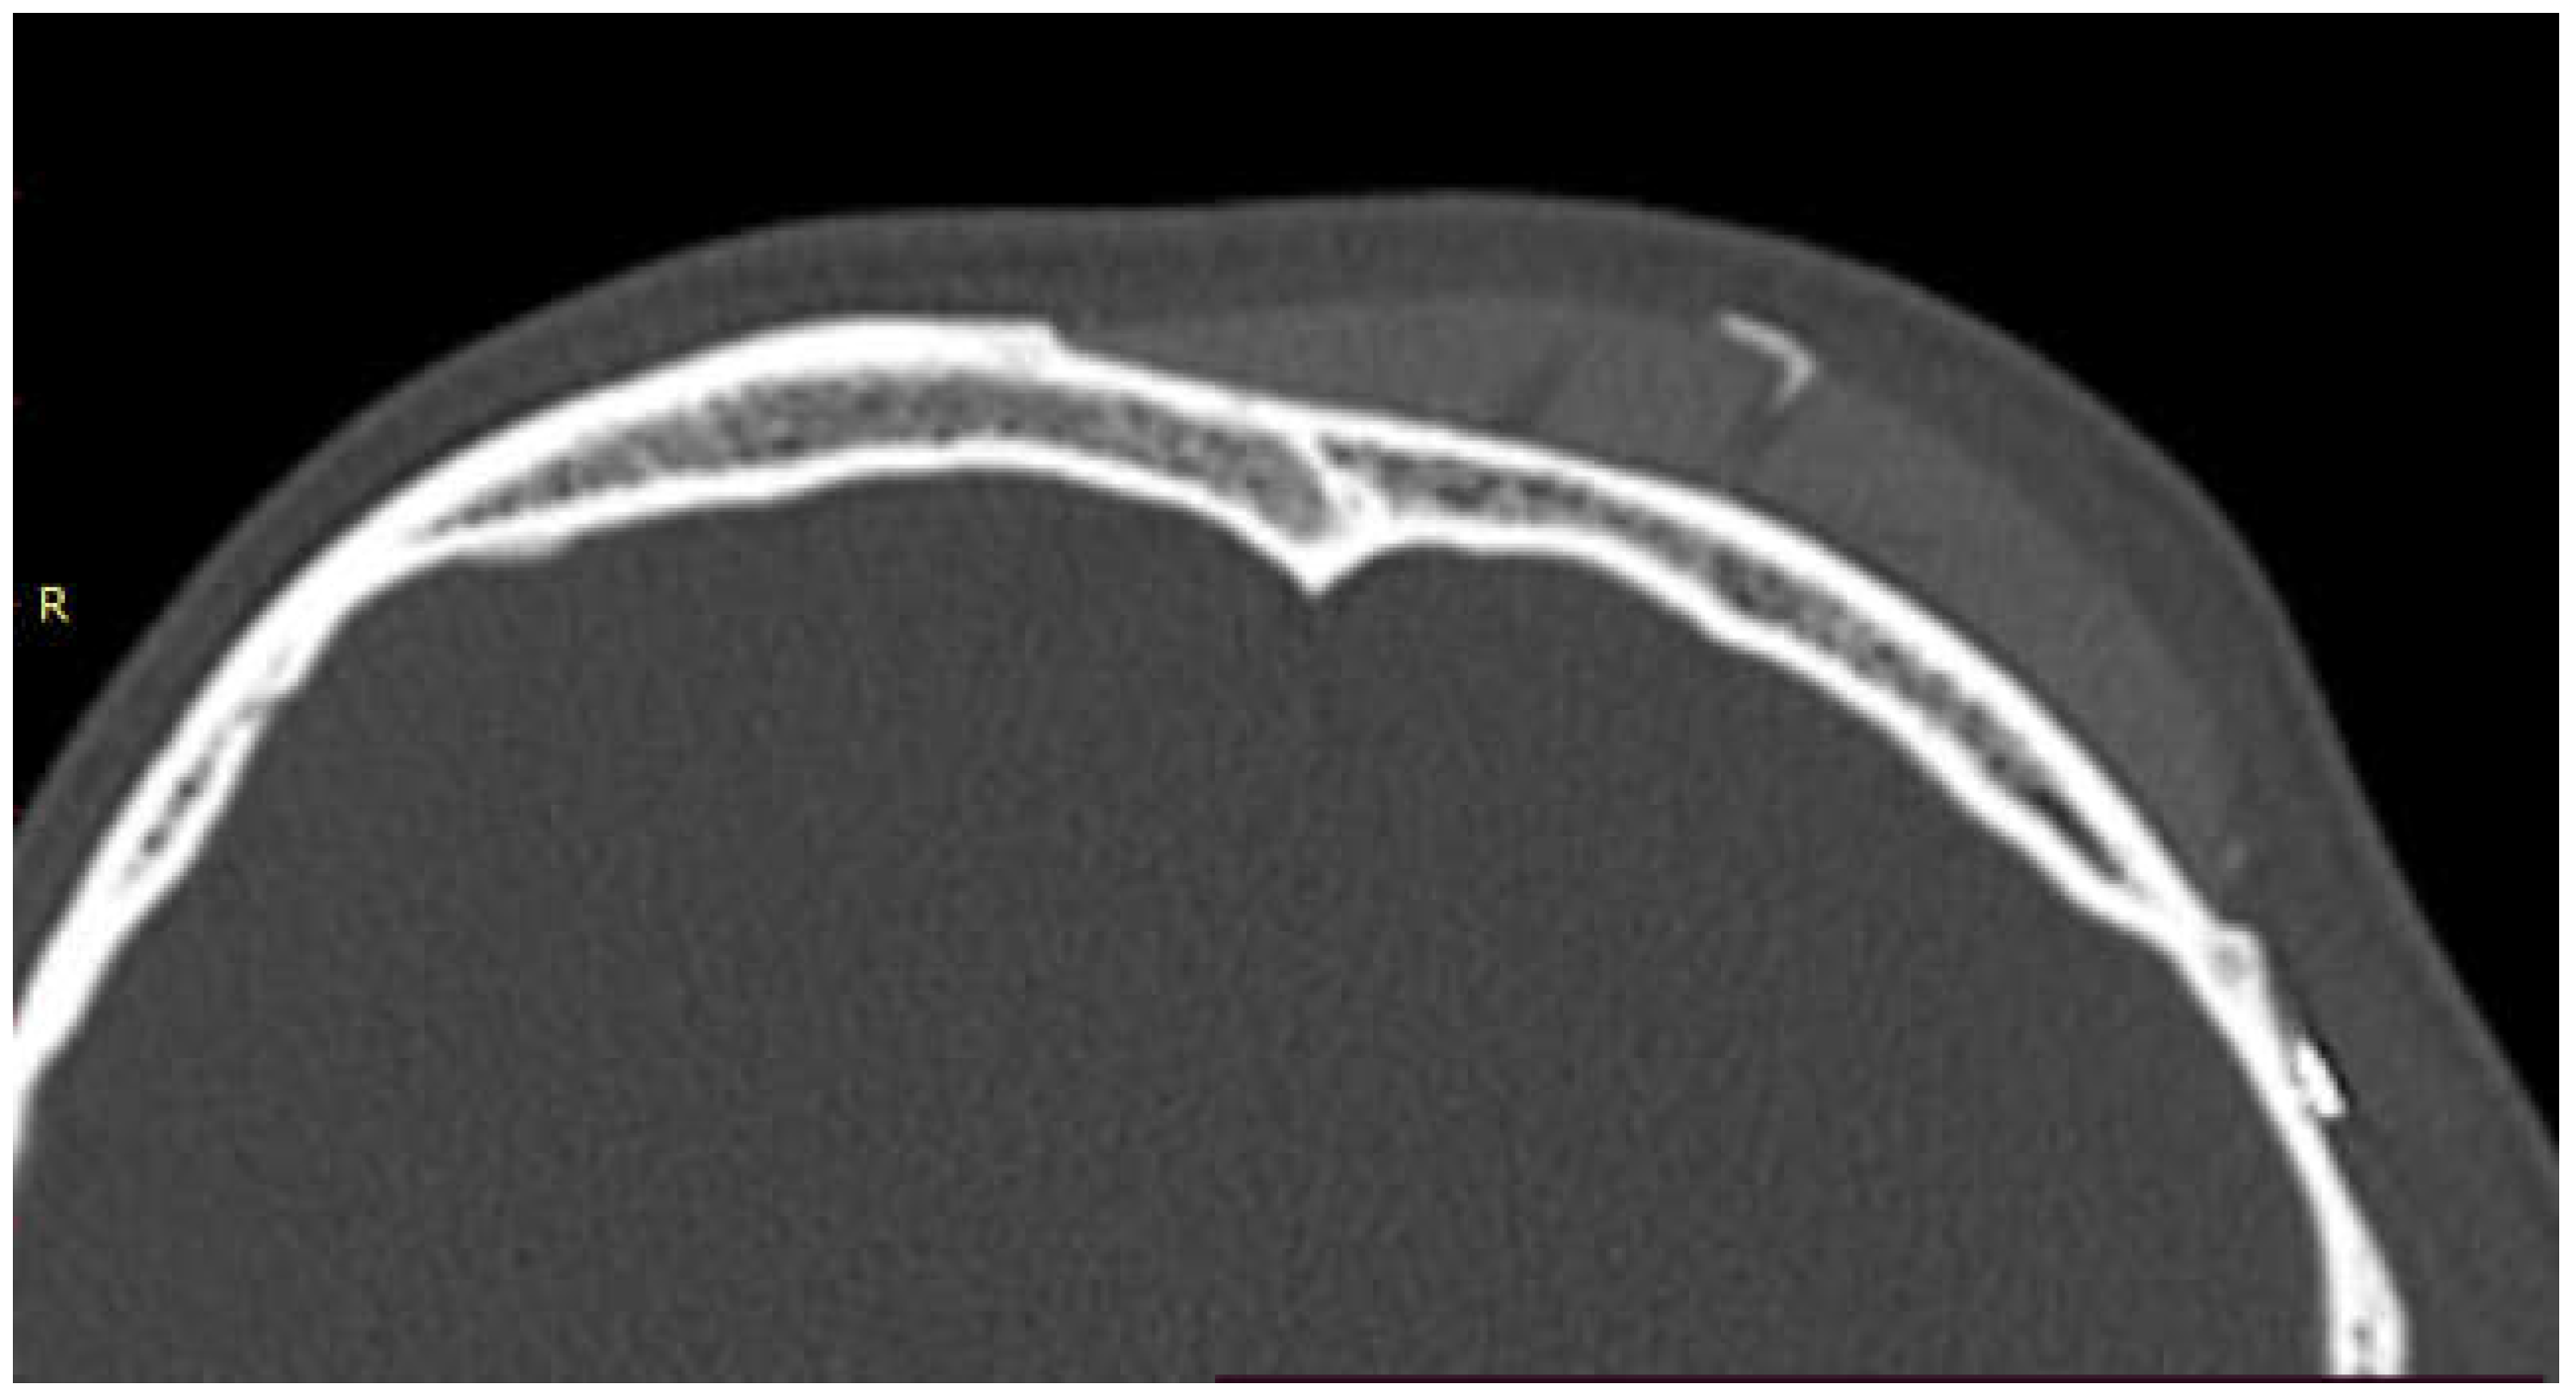

The one case in which bone regrowth was not noticeable is a female patient where complex mandibular implants were designed with a very small bone/implant interface. No signs of bone resorption were noted at bone/implant interface.

The case of maxillofacial surgery where bone regrowth was not observable underscores the importance of a sufficient bone prosthesis interface for a successful osteointegration (see Figure 3). The neurosurgical case series, in which the interface between bone and prosthesis for cranioplasty is minimal, further corroborated this statement. Studies have shown that a larger contact area between the implant and bone facilitates osteoblastic activity and bone ingrowth [44]. In addition, that implants with roughened surfaces or porous coatings promote greater bone ingrowth compared to smooth-surfaced implants [45,46]. For this reason, factory-created holes are a valuable aid in the creation of bone tissue within them, as demonstrated in the previously analyzed case. Other studies aimed at enhancing the bioactivity of PEEK to improve the bone-implant interface are still in the in vitro stage, but we anticipate significant progress soon [47,48].

Figure 3. The maxillo-facial surgery case representing the absence of ossification, caused by poor interface between bone and prosthesis.